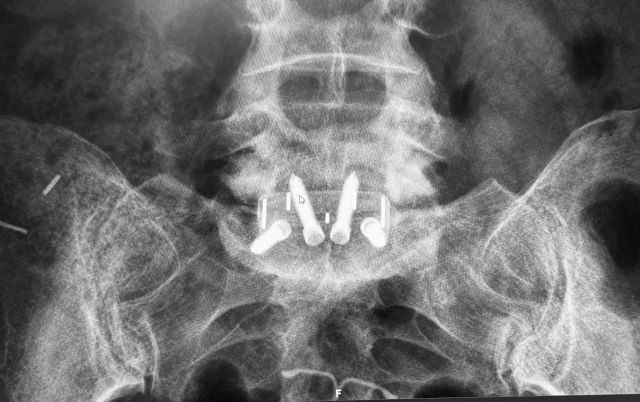

Fusión espinal: En algunos casos, especialmente cuando hay inestabilidad espinal, puede ser necesaria una fusión vertebral para estabilizar la columna vertebral después de la cirugía de descompresión. Esto implica fusionar dos o más vértebras.